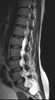

Anterior vertebral scalloping

The vertebral column, also known as the backbone or spine, is part of the axial skeleton. The vertebral column is the defining characteristic of a vertebrate in which the notochord (a flexible rod of uniform composition) found in all chordates has been replaced by a segmented series of bone: vertebrae separated by intervertebral discs. [Source: Wikipedia ]